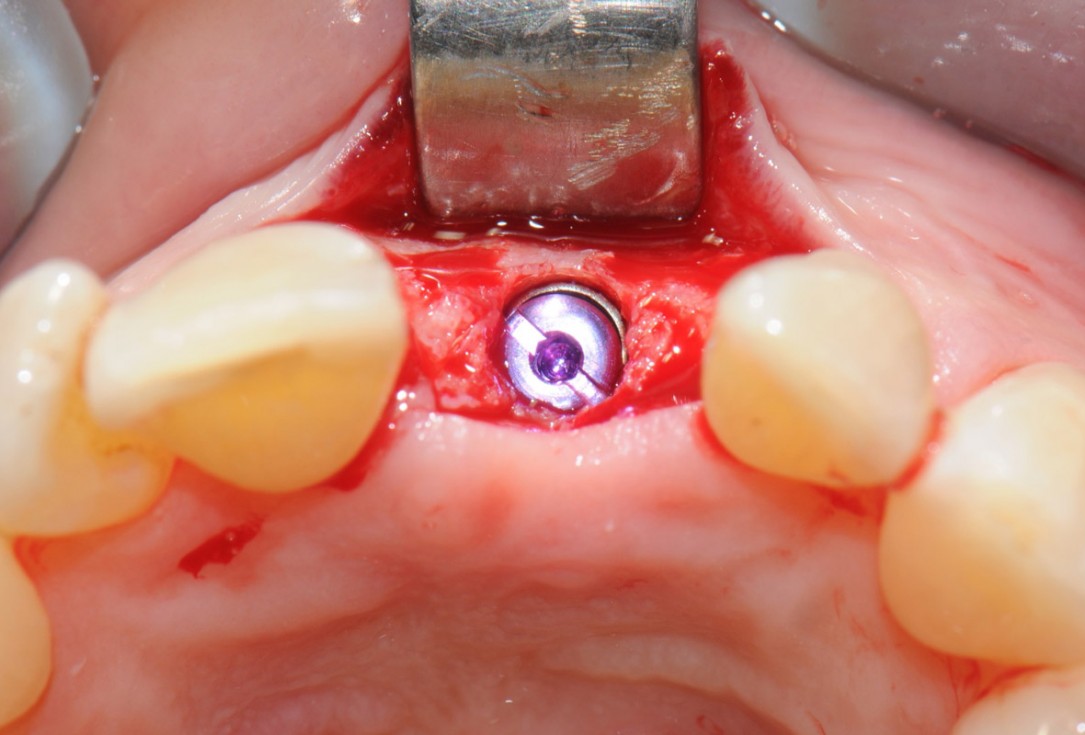

16/18 - Implant placementTooth extraction and socket sealing with mucoderm® - Dr. A. Rossi